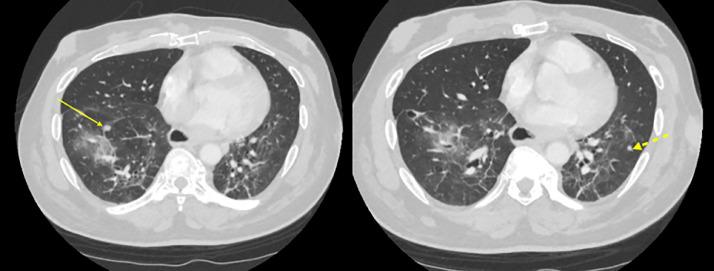

Malignant triton tumors are an extremely aggressive form of malignant peripheral nerve sheath tumor that display rhabdomyosarcomatous features. While these tumors are extremely rare, they have a much higher incidence in patients with neurofibromatosis-1. We present a case of a 64-year-old male with neurofibromatosis-1 who presented to the hospital with sudden worsening of shortness of breath and dysphagia to solids. Radiological examination revealed a large mass in the anterior mediastinum causing significant narrowing and displacement of the upper trachea and esophagus. Biopsy of the mass, done by interventional radiology, demonstrated features of an MTT. The mass was subsequently resected but without confirmation of tumor-free margins and the patient underwent adjuvant radiation therapy. Repeat radiological examination approximately four months later revealed growing malignancy and new metastases, which eventually contributed to the patient's death seven months after his presentation to the hospital.

恶性蝾螈瘤是一种极具侵袭性的恶性外周神经鞘瘤,具有横纹肌肉瘤特征。虽然这些肿瘤极为罕见,但在1型神经纤维瘤病患者中的发病率要高得多。我们报告一例64岁患有1型神经纤维瘤病的男性患者,他因突发呼吸急促和吞咽固体食物困难加重而入院。影像学检查显示前纵隔有一个大肿块,导致上气管和食管明显狭窄和移位。通过介入放射学对肿块进行活检,显示为恶性蝾螈瘤特征。随后切除了肿块,但未确认切缘无肿瘤,患者接受了辅助放疗。大约四个月后重复影像学检查发现肿瘤进展且出现新的转移灶,最终导致患者在入院七个月后死亡。